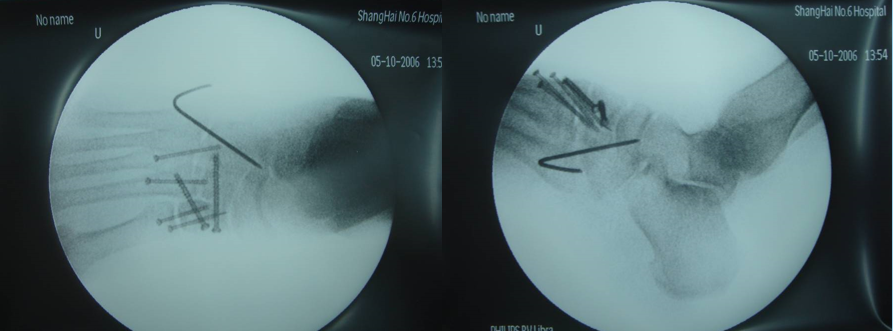

手术治疗Lisfranc损伤有两个手术时间窗,即伤后6-8h和伤后7天后。

如果不能在伤后6-8小时手术,应耐心等待,待患足肿胀消退出现褶皱时再行手术治疗。若冒然进行手术,可能会加重术后肿胀,或者皮肤不愈合以及皮瓣因压力过大而坏死。

切开复位内固定急诊手术指征:开放性骨折;血管神经损伤(足背动脉);骨筋膜室综合症。

内固定选择1、克氏针:优点是手术简单、时间短、对周围组织损伤小,缺点是固定不坚强、复位丢失等情况时有发生。2、可吸收螺钉:优点是不需行二次手术取出内固定物,缺点是固定强度不及传统螺钉3、小螺钉系统:经典 --- 3.0mm、3.5mm、4.0mm4、空心螺钉:3.0mm、4.0mm、4.3mm 、4.5mm5、微型钢板:跨关节固定,对于严重的跖骨粉碎性骨折的患者,螺钉无法固定时,建议选择微型钢板桥接固定6、骑缝钉

手术切口选择单一切口、双切口

双切口能充分显露所有的跖跗关节;第一切口位于第一、二跖骨之间。该切口利用了两个间隙,一个拇长伸肌腱内侧,一个为拇短伸肌腱外侧。分别可显露第一跖骨、内侧楔骨和第二跖骨、中间楔骨。通过延长皮肤切口,可以直视第三跖骨和外侧楔骨。第二切口位于第四、五跖骨之间,可以显露其与骰骨之间的关节。

根据三柱理论1、首先复位内侧柱并临时固定 2、再复位固定中间柱3、如外侧柱移位可能需双切口

手术从第一跖骨和内侧楔骨开始。首先直视下复位该关节,评价楔骨之间的稳定性,关节囊通常撕裂,但仍然需要掀开以充分显露关节,清除关节内的软组织和软骨碎片内侧柱稳定后,开始处理第二跖骨和中间楔骨。点式复位钳由第二跖骨基底部外侧远端斜向内侧楔骨内侧面的近端夹持,注意避免第二跖骨向下移位,发生复位不良。

若楔间关节仍不稳,可使用楔骨间螺钉;固定内侧两跖骨后,通常第三跖骨已经足够稳定,若仍未复位,可以参考第一跖骨固定方法固定。通过第二切口固定第4、5跖骨。可以使用克氏针固定。

Lisfranc损伤骨折复位标准:1、C形臂透视显示正、侧、斜位均为正常解剖复位2、如复位后第1、2跖骨基底间隙和内、中楔骨间隙<2mm,跖跗骨轴线<15°为近解剖复位,可以接受,超过这个范围的移位则无法接受3、复位好后,沿第一跖骨轴线向内侧楔骨逆行拧入一枚4.0mm皮质骨螺钉。螺钉由关节远侧1.5-2.0cm处进入,平行于足底或略向跖侧。

4、从内侧楔骨向第二跖骨置入一枚螺钉,重建韧带。螺钉自内侧楔骨近端的背侧置入,指向第二跖骨背侧皮质的下方,螺钉应通过4层皮质,确保对第二跖骨的双皮质固定